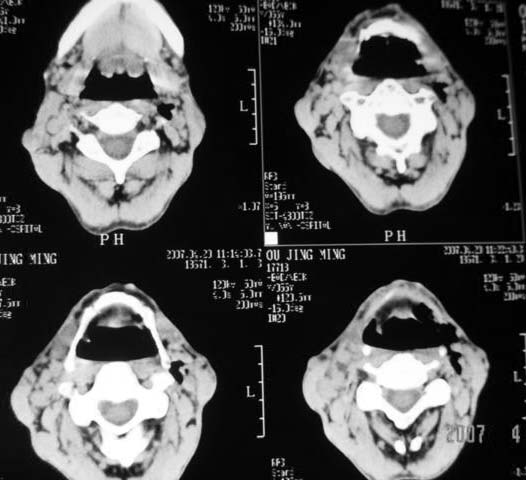

以下是引用dyqct在2007-4-20 16:19:00的发言:[br]考虑:1、左侧梨状窝区破裂伴左颈深、浅部气肿。[br] 2、右侧甲状腺区血肿(请追问病史是否伤及右颈部)。[br] 3、建议病情稳定后增强扫描除外右侧甲状腺腺瘤。